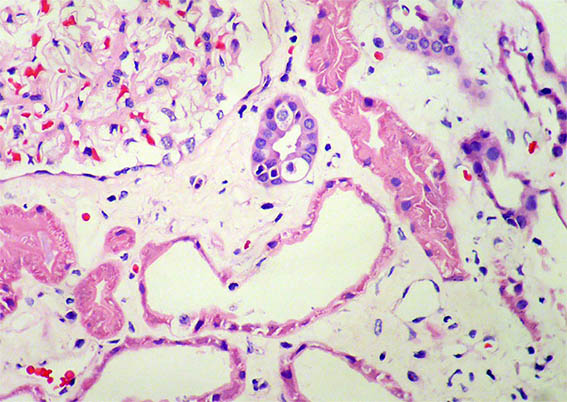

Kidney biopsy is done. Look at the pictures.

Figure 3. H&E, X400.